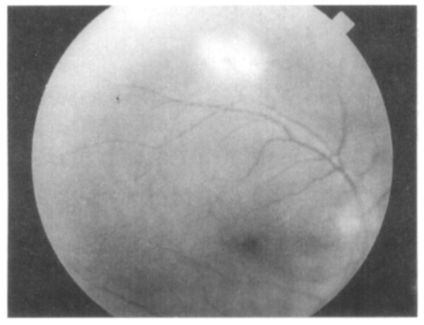

On December 15, 1997, a 60-year-old man visited out-patient clinic at the Department of Ophthalmology, Catholic University of Korea, College of Medicine, due to a decreased and blurred vision in his right eye which persisted for 2 weeks with slight muscle pain. He had no other previous problems with his general health, but he had been treated with oral antihypertensive drugs for 5 years. With a slit-lamp examination, mild inflammatory reaction was detected in the anterior chamber and vitreous body. Through an ophthalmoscopy, one optic disk-sized whitish retinal infiltration was observed in the superior temporal vascular area. One percent of prednisolone acetate (O-LON) solution was applied topically for 10 days (4 times/day). However, retinal infiltration continued to progress and sheath perivascularly on ophthalmoscopy, and hypofluorescent retinal area was detected on a fluorescein angiography. Retinal necrosis was suspected, thus 40 mg of prednisolone (H-LON) was orally administered 3 times a day. Two weeks later, the fundus examination of the right eye showed aggravated inflammation and retinal necrosis as shown in Fig. 1. Oral administration of prednisolone was terminated.

Serological tests for T. gondii were performed by IgG-ELISA and ILA, both of which resulted in strong positives, 1.02 for ELISA with a cut-off value of 0.25 and 1:16,384 for ILA with a cut-off value of 1:32. An oral combination therapy with Fansidar F (25 mg pyrimethamine plus 500 mg sulfonamide, Hoffmann-La Roche, Basel, Switzerland) and prednisolone was carried out for 8 weeks. Five weeks after chemotherapy, inflammatory cells could not be found in the anterior chamber, but there were still one or two positive reactions of inflammatory cells in the vitreous body. The whitish retinal necrotic lesion around the superior temporal vascular area disappeared and the pigmental change in the lesion was observed with the fundus examination. On July 8, 1998, the corrected visual acuity of the right eye improved to 0.63, and there was no inflammatory vitreous opacity. Only clear-cut margin of whitish retinal lesion was observed in the superior temporal vascular area of the right eye. However, antibody titers by ELISA and ILA were still in a high range until now (Fig. 2), dotted rectangle line (labeled by UVS). This is compatible with another chorioretinitis case (dotted circle, labeled by CRS, Choi et al., 1997) as described as limitations of relation between serological examination and the ocular pathology (Holliman et al., 1991), whereas those of lymphadenitis cases appeared to be decreased rapidly in antibody titers (Lym1 of Kim et al., 1993 and Lym2-1, 2-2, and 2-3 of Choi et al., 1997) after chemotherapy.